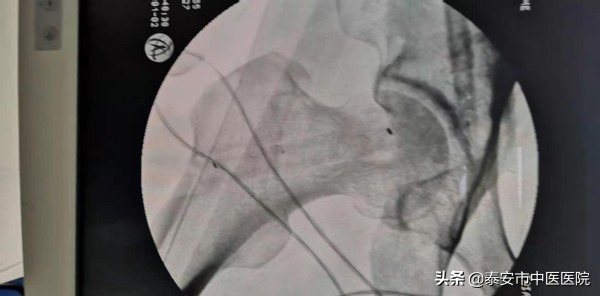

据悉,2月1日上午,*安泰**市中医医院脊柱外科王乃舜团队为71岁男性患者张某(化名)进行了微创髓芯减压加支撑棒植入术,手术效果非常好,术后第二天,患者便可扶拐下地活动。

术后